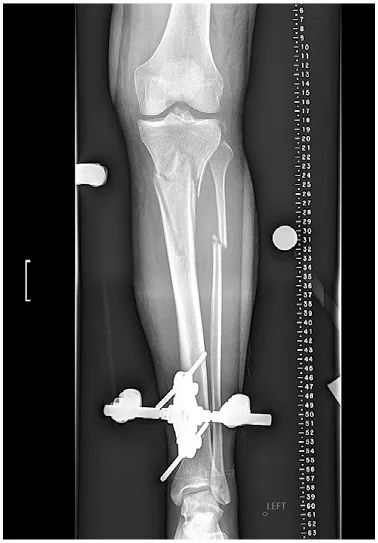

At presentation 1 week after injury, the patient was neurovascularly intact with resolving fracture blisters. The external fixator pin sites showed no evidence of infection. Radiographs showed a complex, largely extra-articular, proximal tibia fracture with dissociation of the tibial tubercle (Fig. 1). Subtle findings of a proximal lateral tibia avulsion fracture (a Segond fracture) and tibial spine comminution raised suspicion for ligamentous knee instability. Diastasis of the proximal fibula from the tibia demonstrated the high energy nature of the trauma. A computed tomography (CT) scan showed the complex proximal tibia fracture with a separate tibial tubercle fragment and confirmed a posterior cruciate ligament (PCL) avulsion fracture and lateral proximal tibia avulsion (Fig. 2). Magnetic resonance imaging (MRI) confirmed a lateral meniscal root tear, disruption of the PCL, proximal tibiofibular capsular ligaments, and moderate posterolateral corner injury (Fig. 3).

Figure 1: Anteroposterior (AP) radiograph shows spanning external fixation.